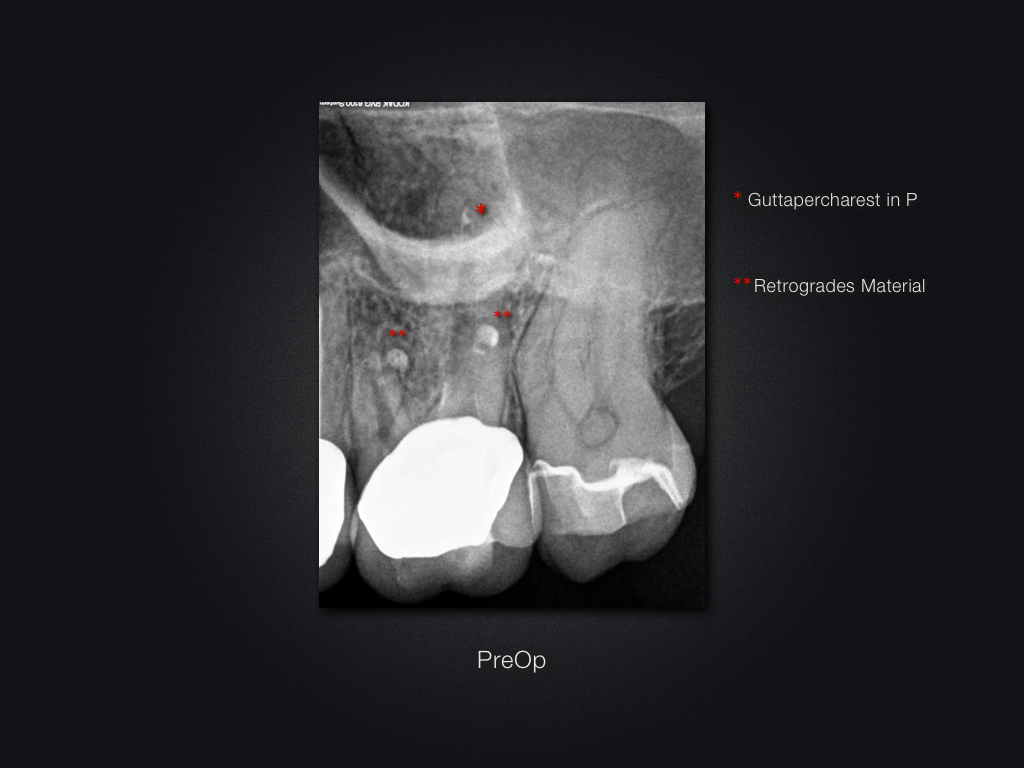

2D vs. 3D (XXVI)